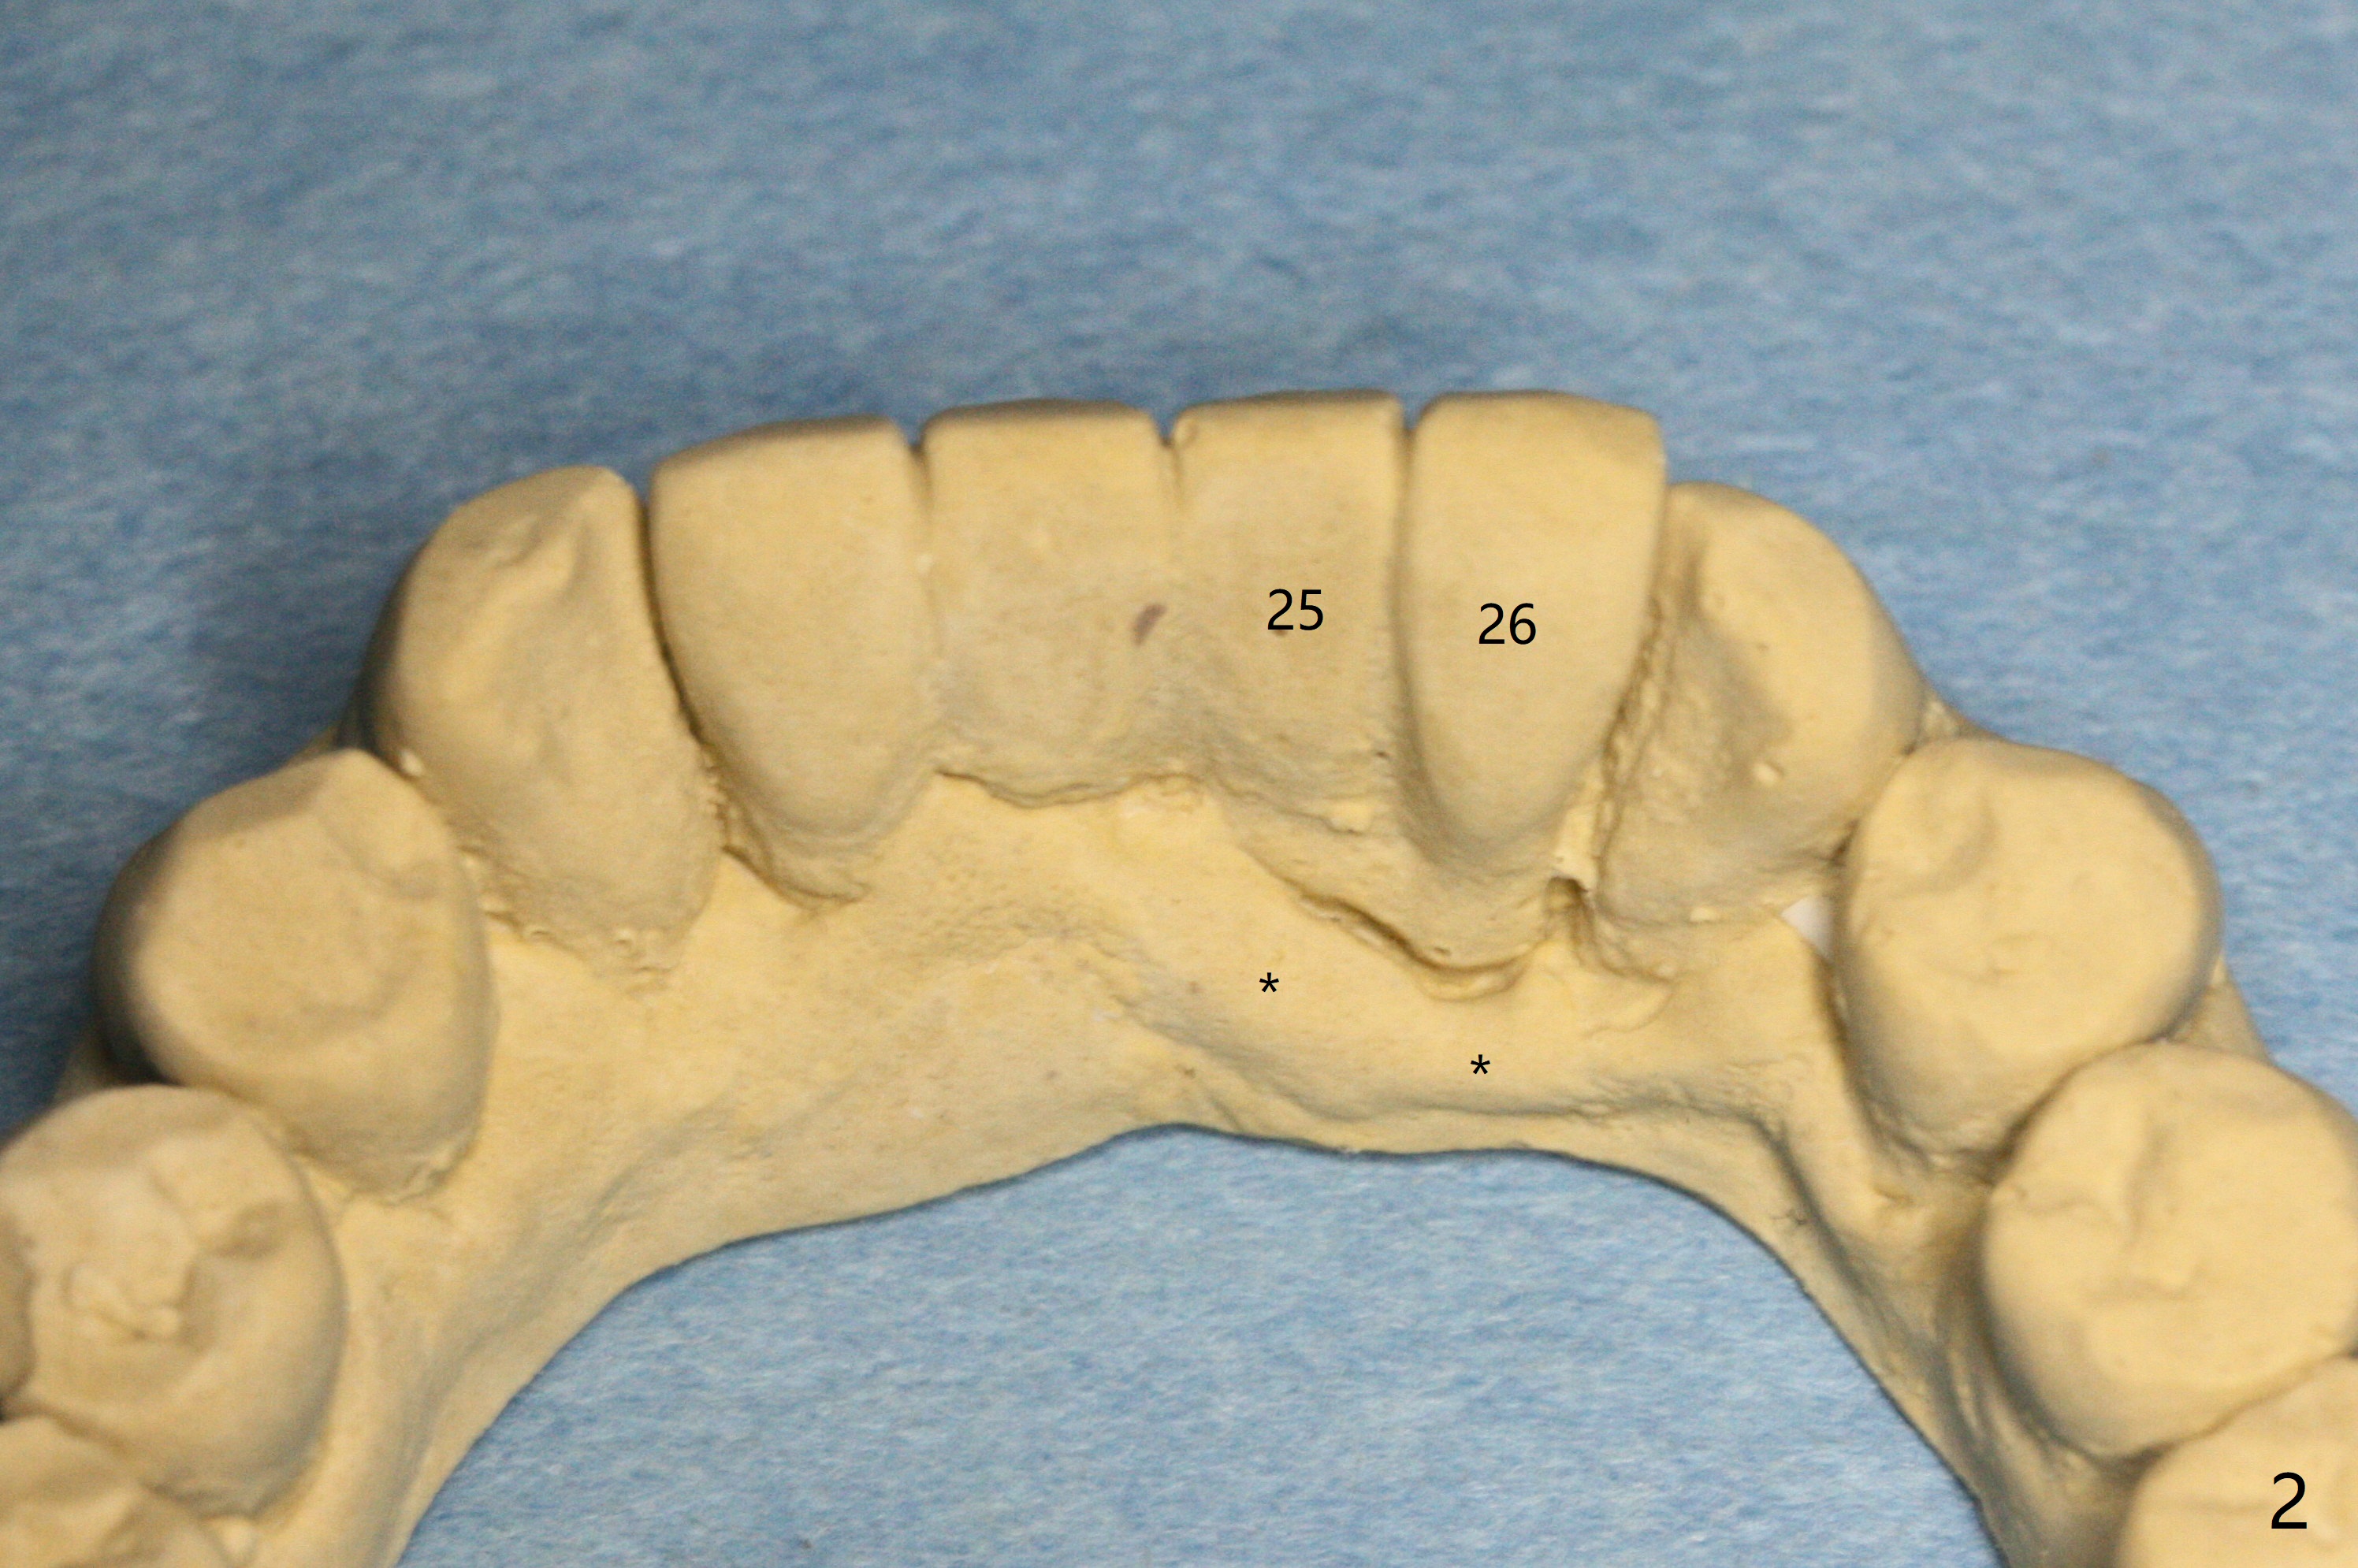

A 58-year-old man with splinted crowns at #23-26 has buccal abscess and lingual gingival recession at #25 and 26 (Fig.1,2). Large periapical radiolucency involves all of the 4 incisors (Fig.3). Note residual crestal bone between the incisors (*). It appears that a 1-piece implant with 4 mm cuff (Fig.4 pink) should be placed on the right side, while a longer 1-piece implant (23 mm) with shorter cuff (1.5 mm) on the left side. A provisional FPD will be fabricated from a stent.